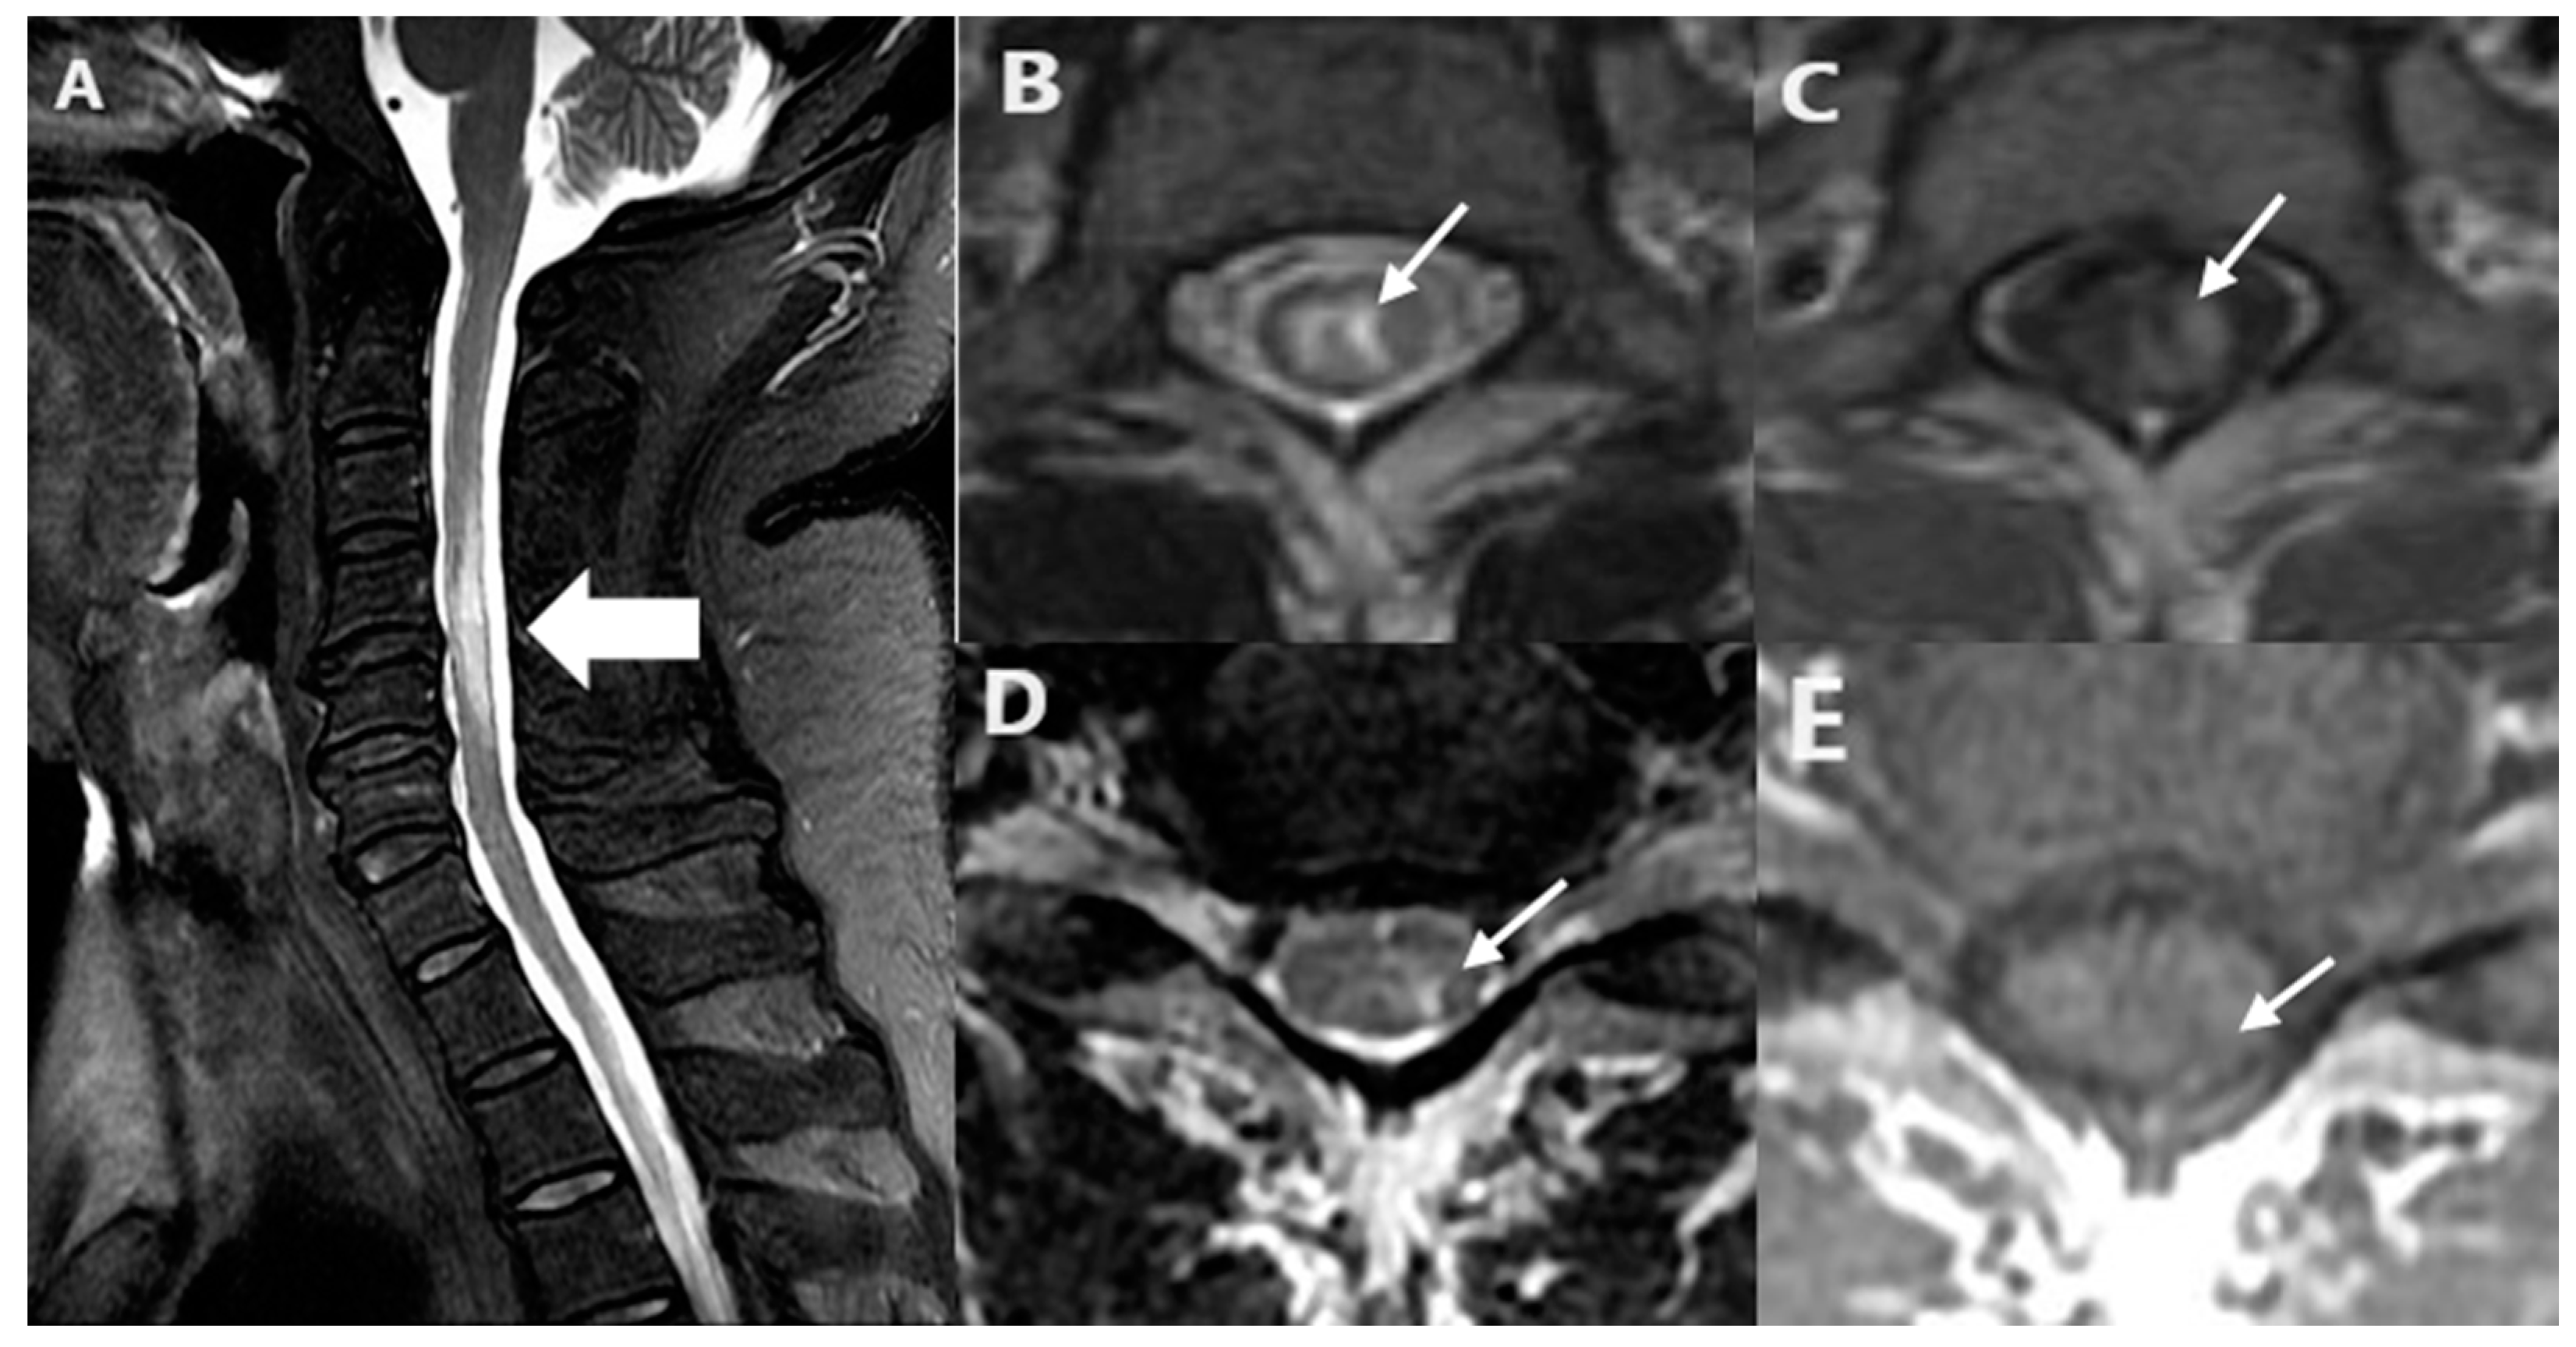

| Bright spotty lesions | 7 (29.2%) | 17 (70.8%) | <0.001 |

| Lesion length (segments) (median, IQR) | 3.0 (2.0–5.0) | 6.0 (3.0–10.0) | 0.003 |

| Gadolinium enhancement (n = 62) | 29 (76.3%) | 24 (100.0%) | 0.010 |

| Central cord involvement | 20 (51.3%) | 23 (95.8%) | <0.001 |

| LETM | 21 (53.8%) | 22 (91.7%) | 0.002 |